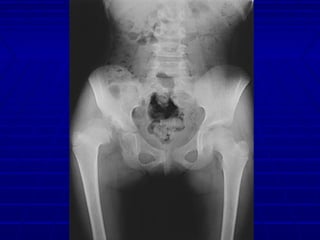

ImagingImaging

 RadiographsRadiographs

Radiographs SummaryRadiographs Summary

 Femoral head appears 4 - 7 monthsFemoral head appears 4 - 7 months

 Shenton’s lineShenton’s line

 Perkin’s and Hilgenreiner’s linesPerkin’s and Hilgenreiner’s lines

 Inferomedial quadrantInferomedial quadrant

 Center Edge Angle (< 20 abnormal)Center Edge Angle (< 20 abnormal)

 Acetabular indexAcetabular index

 Normal < 30 (Weintroub et al)Normal < 30 (Weintroub et al)

 Tear drop*Tear drop*

 Abnormal widening in DDHAbnormal widening in DDH

*may be only sign in mild subluxation*may be only sign in mild subluxation